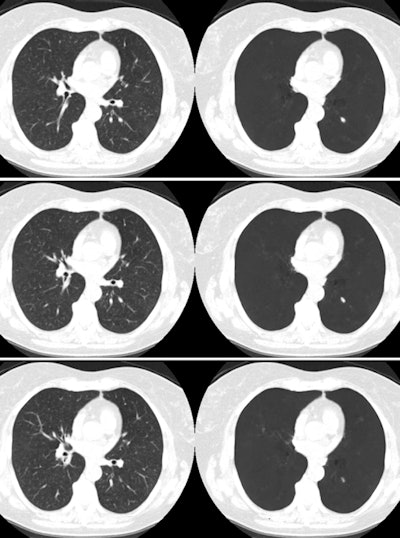

By suppressing vessels from lung cancer screening CT scans, a computer-aided detection (CAD) algorithm helped radiologists improve their ability to spot nodules as well as reduce their interpretation times, according to an article published in the March issue of the American Journal of Roentgenology.

Addressing this specific obstacle, Lo and colleagues developed a function for CAD software (ClearRead CT, Riverain Technologies) that subtracts vessels from chest CT scans as it searches for lung nodules. The software received 510(k) clearance from the U.S. Food and Drug Administration (FDA) in 2016.

"Whereas CAD systems focus on the characteristics of the nodule to make a determination of a positive result, vessel subtraction removes vessel clutter and structural complexities surrounding the nodule, potentially decreasing the likelihood that a [false-positive] result will occur," they wrote.